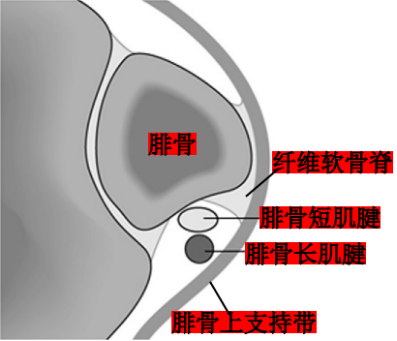

腓骨长短肌位于小腿外侧间隔。

腓骨长肌(PL):起于腓骨头、腓骨外侧面上2/3和小腿深筋膜,止于第1跖骨外侧及毗邻的第1楔骨的内侧,至小腿下1/3处,长肌移行为肌腱,在它到达止点前的行程中有三个弯曲,第一个在外踝顶点,第二个在跟骨外侧壁的腓骨肌滑车下,第三个在骰骨结节处经90°转到足底。

腓骨短肌(PB):起于腓骨外侧面下2/3及前后肌间隔,短肌至外踝的后下方始为移行为肌腱,紧贴于外踝后方,通过外踝顶点转向足外侧前方,经过跟骨外侧壁腓骨肌滑车上方最后止于第五跖骨基底。

腓骨肌腱鞘:起于外踝顶点上3.5cm并向远端延伸4cm,在腓骨的远端,腱鞘分为两部分,腓骨长、短肌腱各自进入独立的滑液鞘。

腓骨外踝窝:外踝的后方近端较宽广,远端呈锥形变小并有一浅的沟。

纤维软骨脊(FCR):腓骨外踝窝的外侧缘有一纤维软骨形成的缘,构成了窝的结构。该纤维软骨脊近端明显,向远端渐变小,使得沟的整体深度增加了2-4mm,且形状更适于容纳腓骨肌腱,从而促进应力分散。

腓骨肌支持带:

腓骨上支持带(SPR):起于腓骨外侧面和腓骨外踝窝,绕过腓骨肌腱后止于跟骨和跟腱外侧。SPR没有直接牢固固定于纤维软骨脊,而是与腓骨外侧面的骨膜融合。

下支持带(IPR):前上方与伸肌支持带外侧根延续,后下方附着于跟骨前部外侧面。在跟骨滑车上下形成两个纤维管道固定肌腱于跟骨外侧壁。

相关文献在单纯切断下支持带后,腓骨肌腱的稳定性不受影响,但单纯切断上支持带后,将跟骨外翻后腓骨肌腱有脱位趋势。因此认为:腓骨肌上支持带是稳定腓骨肌腱的重要结构。

腓骨外踝窝、纤维软骨脊和腓骨上支持带是稳定腓骨肌腱的基本结构。其中又以腓骨肌上支持带最为重要。